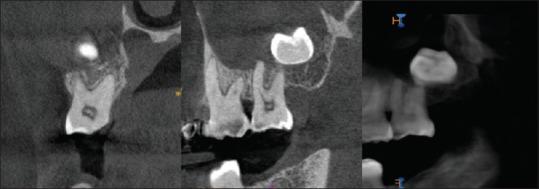

Maxillary third molars are one of the most commonly impacted teeth, but its inverted type is very rare. Five cases of inverted and impacted maxillary wisdom teeth are described here. Two were symptomatic and required transalveolar extractions, while three were conservatively managed. Complications may arise from surgical removal of inversions, and so, removal must be carefully weighed against the benefits of retaining them. This case series discusses the rare occurrence of impacted inverted maxillary third molars, its increased incidence in the Indian population, and the dilemma considering its treatment options. If left untreated, regular follow-up should be done to note for any complication.

上颌第三磨牙是最常见的阻生牙之一,但其倒置型非常罕见。本文描述了5例倒置阻生的上颌智齿。其中2例有症状,需要经牙槽拔除,另外3例采取保守处理。手术拔除倒置牙可能会出现并发症,因此,必须仔细权衡拔除与保留的利弊。本病例系列讨论了上颌第三磨牙倒置阻生的罕见情况、其在印度人群中发病率的增加以及考虑其治疗方案时的困境。如果不进行治疗,应定期随访以注意是否出现任何并发症。